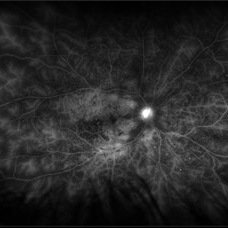

Central Retinal Vein Occlusion with Severe Ischemia

Composite fluorescein angiogram of the left eye of a male with a Central Retinal Vein Occlusion with severe ischemia.

Photographer: Olivia Rainey

Imaging device: Heidelberg Spectralis

Condition/keywords: central retinal vein occlusion (CRVO), composite, fluorescein leakage, ischemic CRVO